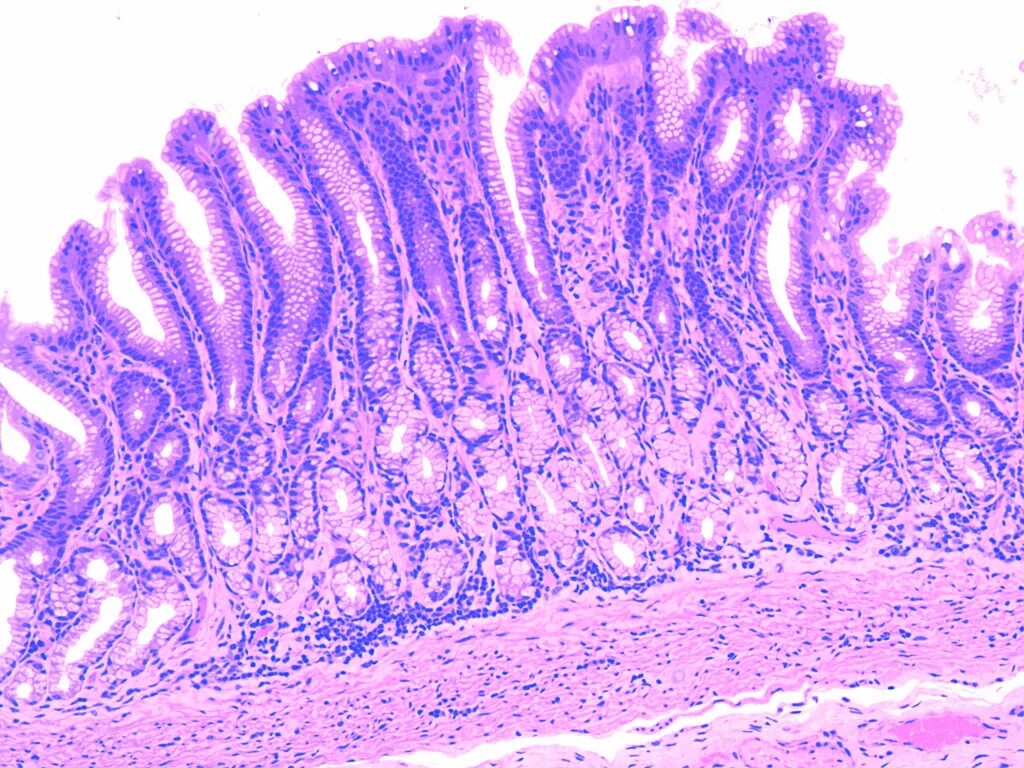

Гистология слизистой оболочки